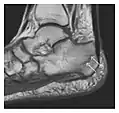

Figure 7: Fatigue fracture of the talus in a 25-year-old male basketball player with right hind foot and ankle pain, without history of trauma, and a normal initial radiograph (not shown). (a) One-month followup lateral radiograph shows normal appearance. (b) Sagittal T1-weighted MRI shows an irregular fracture line (arrow) within an ill-defined area of hypointensity corresponding to bone marrow edema.[1]